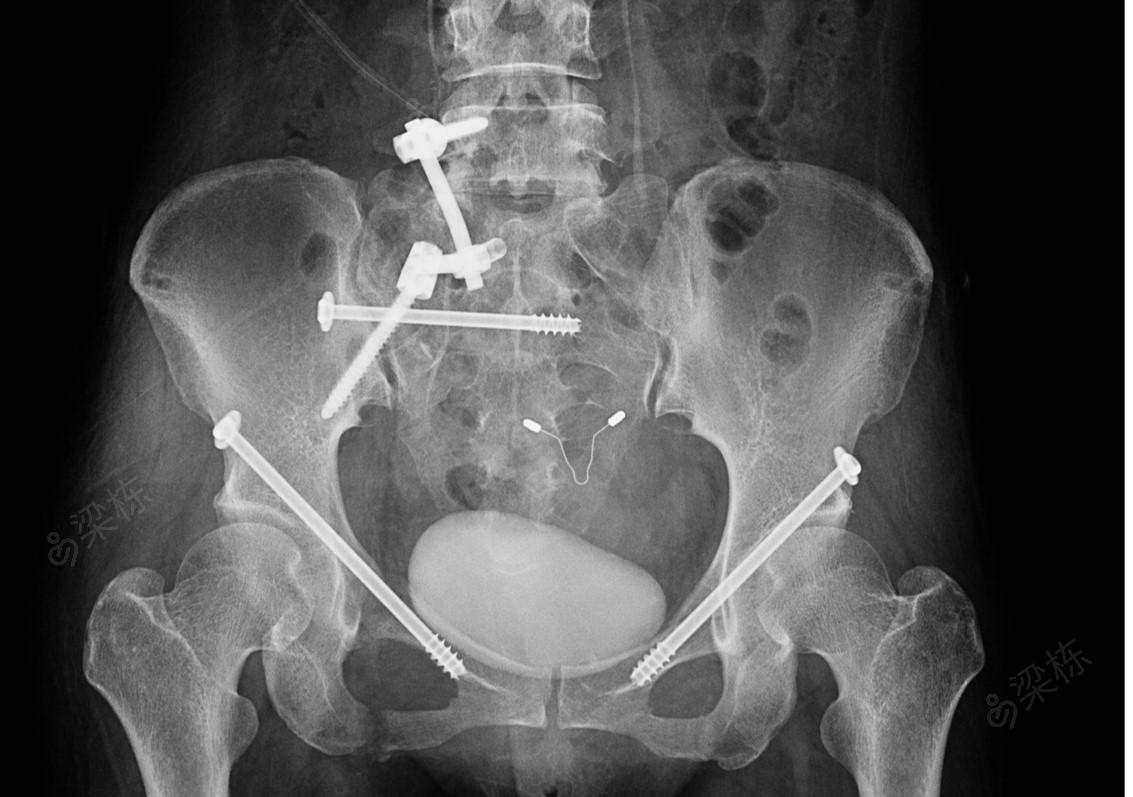

讨论这个骨盆骨折手术做的怎样

图片尺寸1600x1200